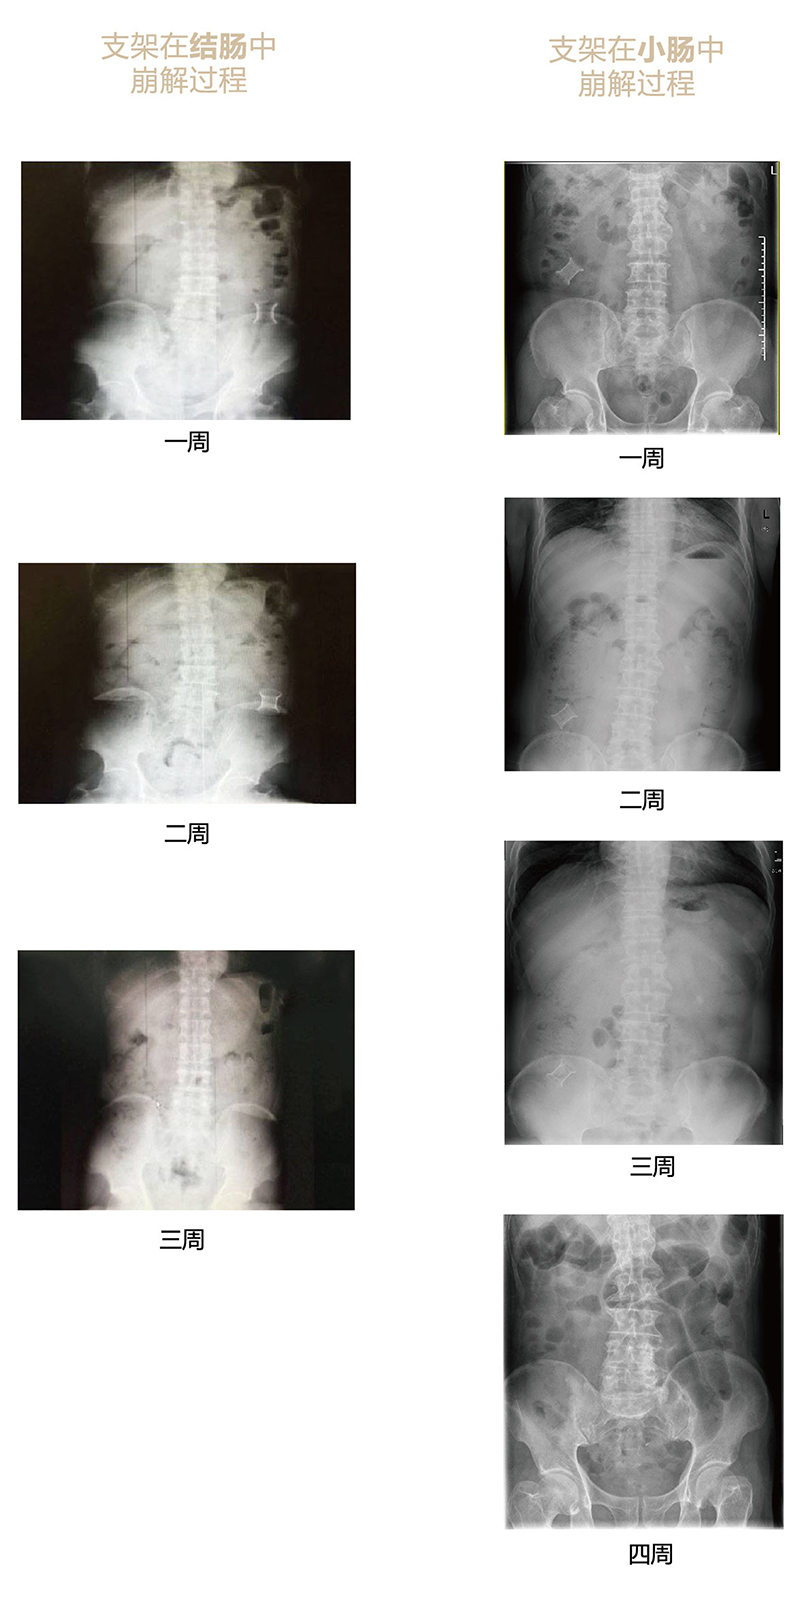

“可崩解腸道吻合器”由聚乙醇酸(PGA)與硫酸鋇按重量比7:1混合注塑制成,在X線下顯影,可動(dòng)態(tài)追蹤可崩解腸道吻合器(支架)在腸道內(nèi)崩解過程。

為解決該問題,蔡秀軍教授在“支架法空腔臟器吻合技術(shù)”的理念基礎(chǔ)上,又發(fā)明了“蔡氏腸轉(zhuǎn)流術(shù)”,這是一種應(yīng)用“可崩解腸道吻合器HB型(可崩解腸轉(zhuǎn)流支架)”(發(fā)明專利號:201910794214.3),的支架法腸道轉(zhuǎn)流術(shù),此創(chuàng)新術(shù)式既能保護(hù)低位吻合口,更避免了回納術(shù)。可崩解腸轉(zhuǎn)流支架在直腸癌根治術(shù)中植入遠(yuǎn)端回腸,可確保完全阻斷腸腔,用腸造瘺管在轉(zhuǎn)流支架近端行腸造瘺,起到完全轉(zhuǎn)流的作用。腸轉(zhuǎn)流支架在二至三周內(nèi)逐漸崩解,并在四周內(nèi)完全排出體外,恢復(fù)腸道通暢后拔除造瘺管,避免了傳統(tǒng)造口回納的二次手術(shù)。該創(chuàng)新術(shù)式具有方法簡單、吻合時(shí)間短、人體內(nèi)無異物永久殘留、不破壞吻合口粘膜下血管,并能預(yù)防吻合口漏、可避免人工肛門留置及二次手術(shù)、治療周期可縮短至二至四周、患者生理心理創(chuàng)傷顯著減少。